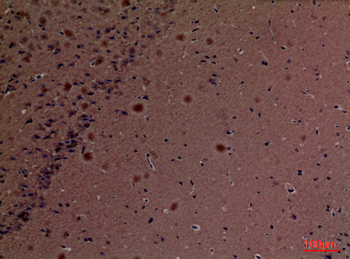

Anti-Cyclophilin A/PPIA Antibody [orb19174]

FC, ICC, IF, IHC, IHC-Fr, WB

Human, Mouse, Rat

Rabbit

Polyclonal

Unconjugated

10 μg, 100 μgCYPA Rabbit Polyclonal Antibody [orb100498]